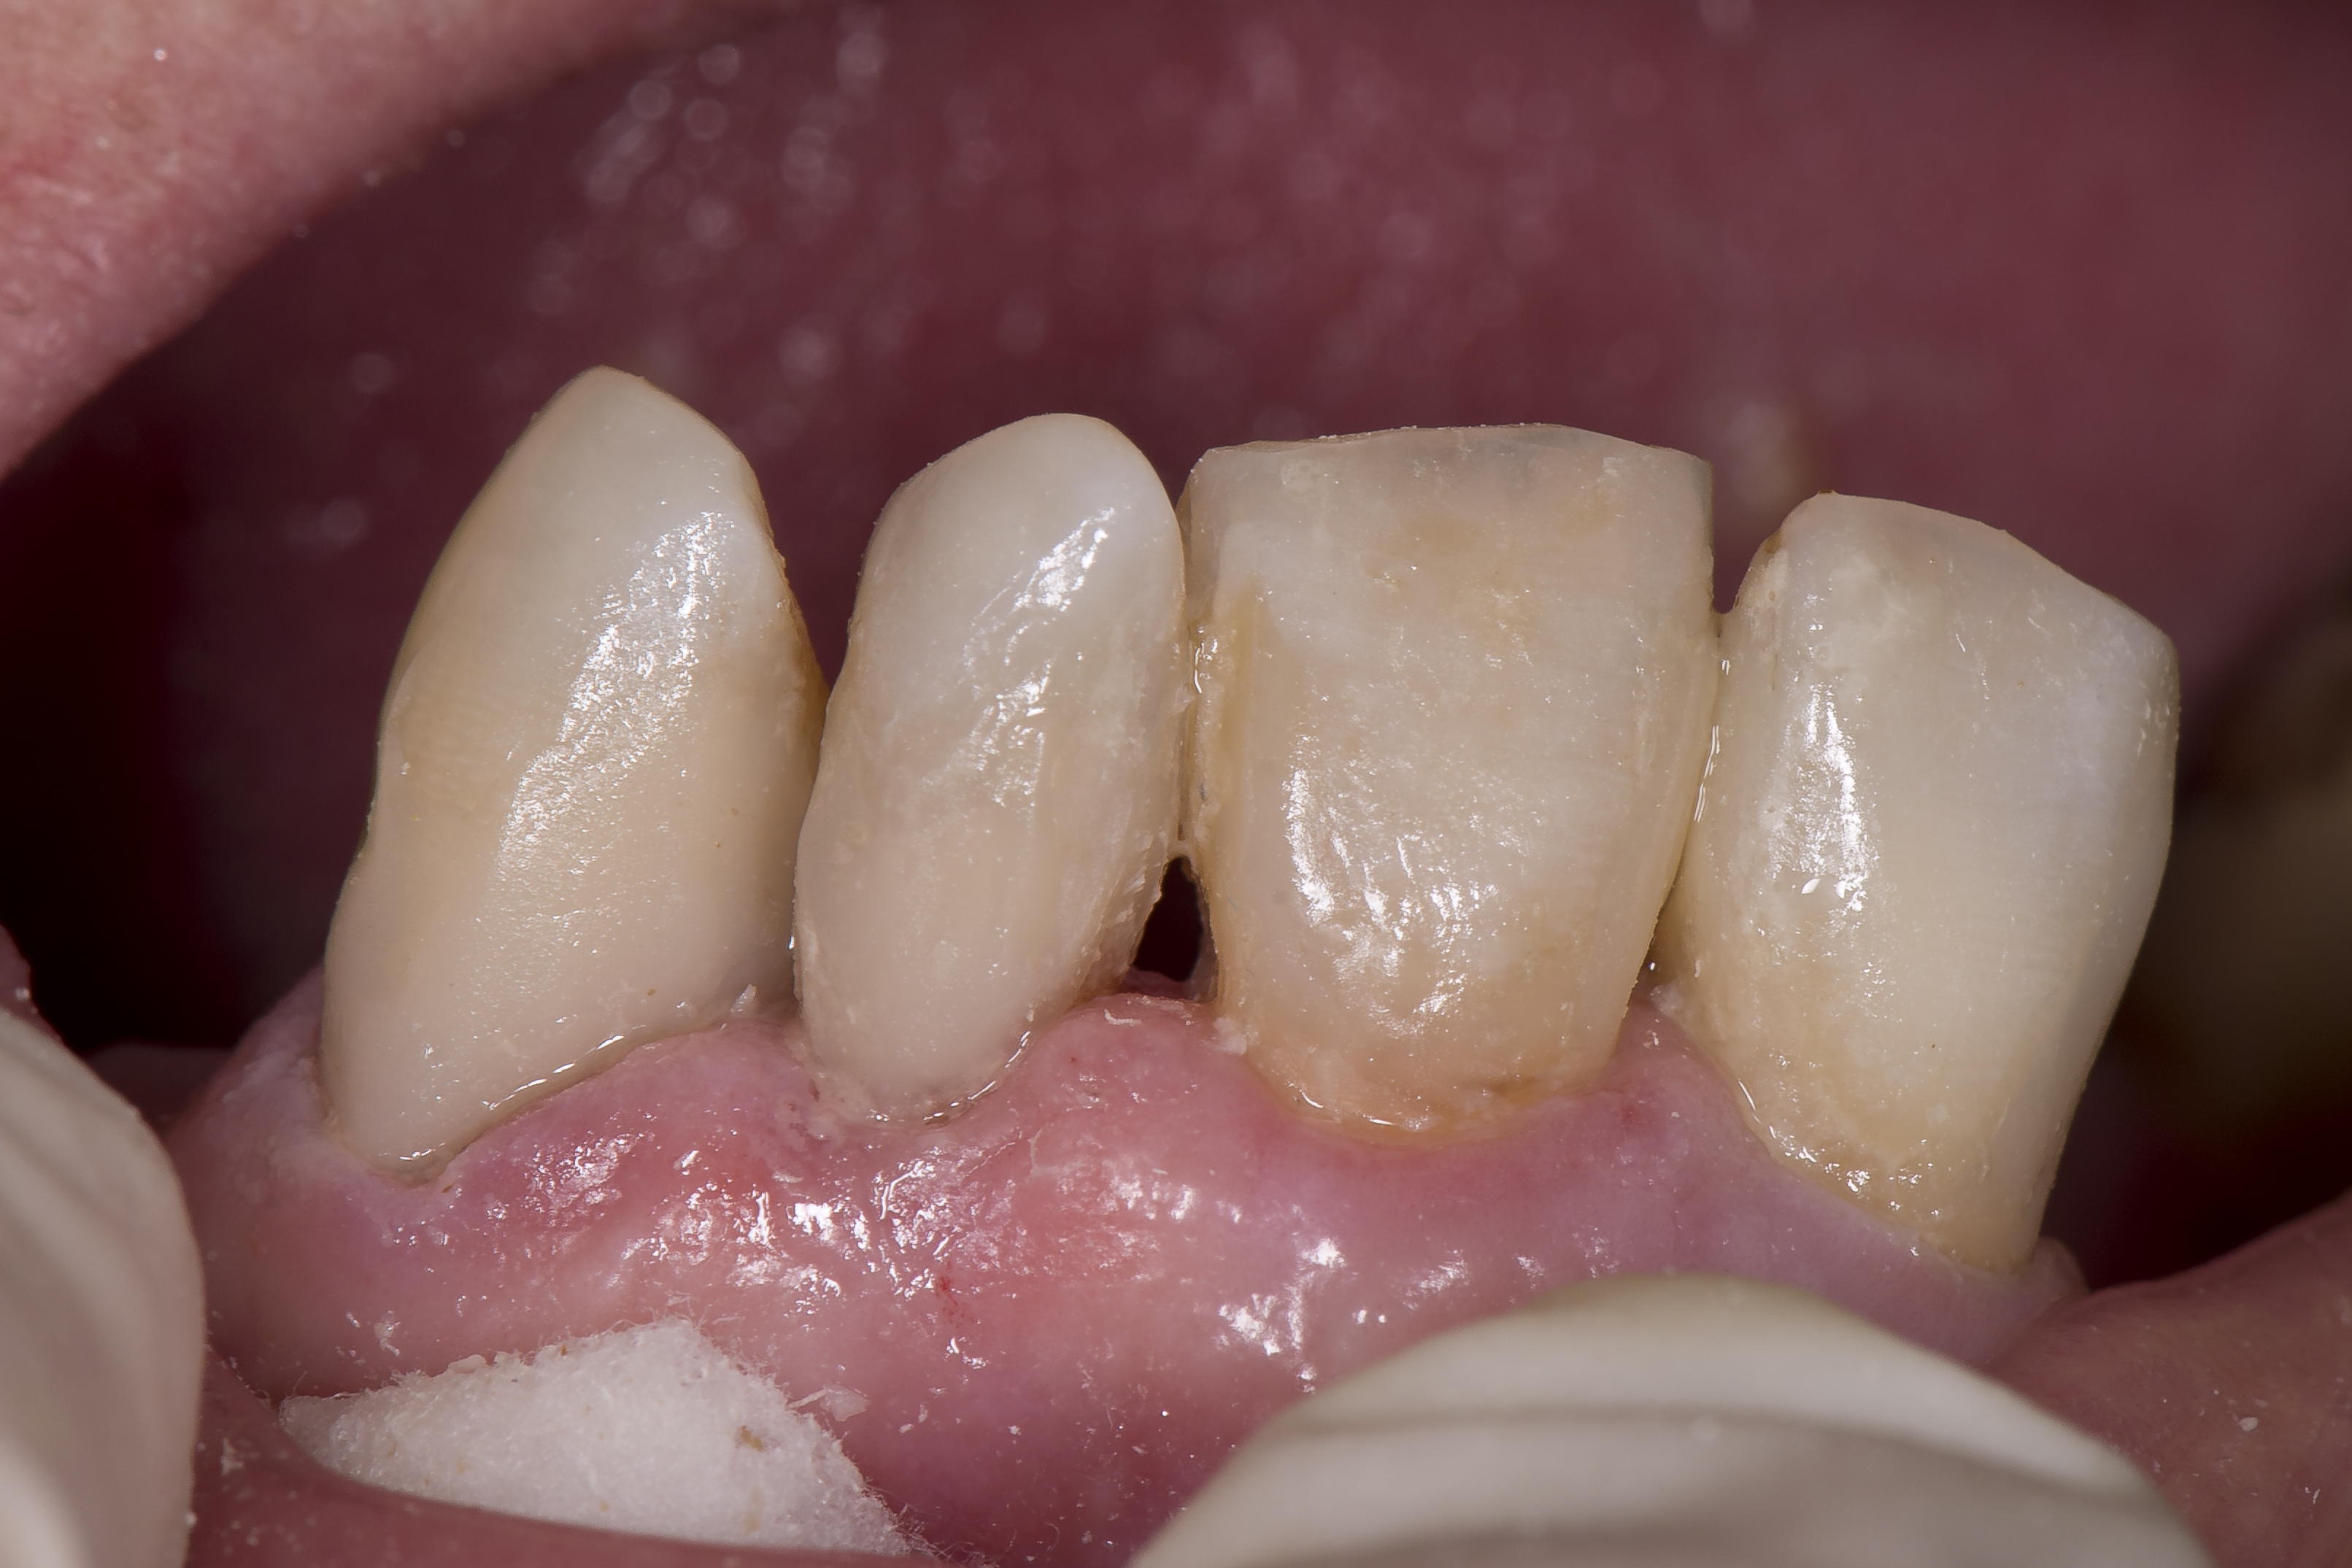

Poniżej przedstawiono przykład kliniczny leczenia z wykorzystaniem materiału OptiShade (Kerr), w którym technologia efektu kameleona połączona jest z efektem dodatku barwnika, co daje do dyspozycji lekarzowi dentyście trzy różne kolory w zależności od odcienia zęba. Do gabinetu stomatologicznego zgłosiła się pacjentka w wieku 73 lat użytkująca protezy ruchome. Powodem zgłoszenia była chęć poprawy estetycznej wyglądu zębów oraz poprawa utrzymania protez w jamie ustnej (ryc. 4).

Ryc. 4. Stan uzębienia pacjentki przed rozpoczęciem leczenia z widocznymi, obfitymi złogami płytki nazębnej.

Badanie wykazało znaczące braki w higienie jamy ustnej, które przyniosły skutek w postaci rozwoju ubytków próchnicowych pierwotnych w obrębie wszystkich powierzchni zębów 11, 21, 22, 23 oraz powstaniem próchnicy wtórnej wokół wypełnień. Ponieważ pacjentka użytkowała dolną protezę całkowitą, nie doszło do przeciążenia zębów siecznych w szczęce i zwiększenia ich ruchomości. Rozwój próchnicy spowodował znaczne defekty estetyczne w obrębie zębów przednich, które w pewnym momencie stały się dużym obciążeniem psychofizycznym dla pacjentki (ryc. 5).

Po skończonej polimeryzacji każde wypełnienie było poddane kontroli i ewentualnemu dostosowaniu do warunków zwarciowych – co nie było zbyt problematyczne, biorąc pod uwagę umiejscowienie ubytków. Ostatnim etapem było polerowanie przy pomocy gumek Opti1Step oraz szczoteczek polerujących OccluBrush (Kerr) (ryc. 12).

Ryc. 12. Na zdjęciu widocznych jest ogółem sześć wypełnień kompozytowych wykonanych jednym odcieniem materiału kompozytowego w różnych miejscach różnych zębów i w ubytkach o różnym kształcie i głębokości.